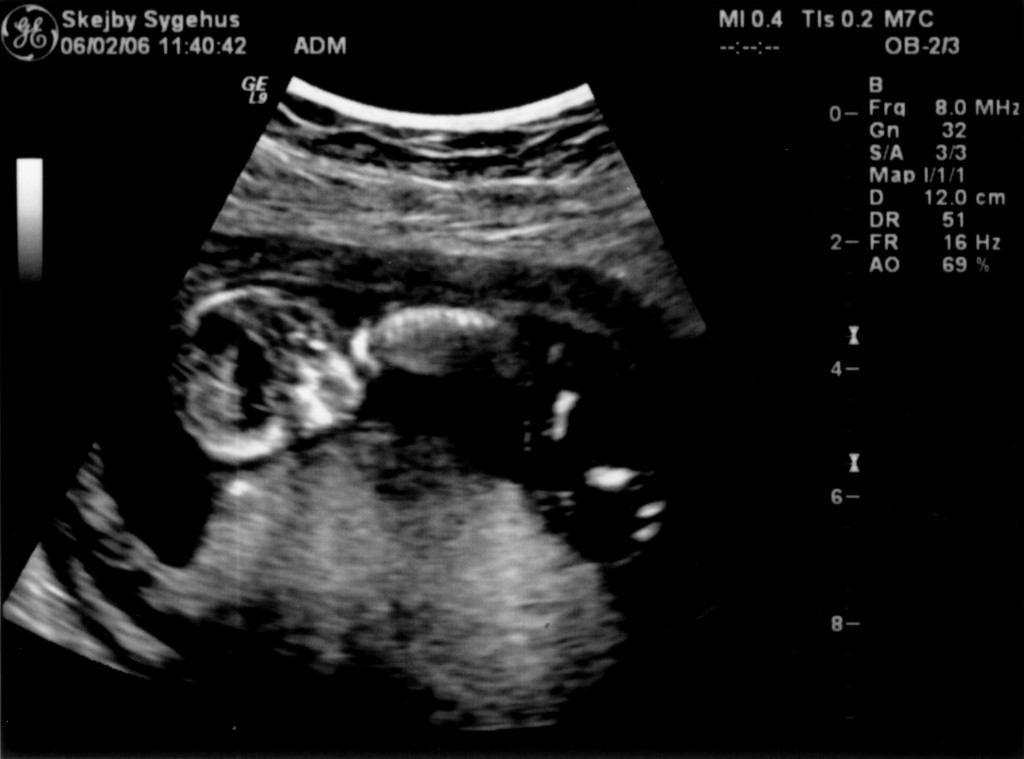

Ultralydsskanning den 22. marts 2006

Vi har så endelig været på Skejby Sygehus, hvor specialisterne skulle vurdere babys hjerte. Konklussionen var at baby og hendes hjerte ikke fejler noget - alt er i den skønneste orden. Der blev foretaget en meget grundig skanning og billederne blev vurderet af en afdelingslæge, en overlæge samt en overlæge med mange års international erfaring i børns hjertefejl. Det var en stor lettelse at hun ikke fejler noget. Baby blev undersøgt generelt en gang til at specialisterne og alt er som det skal være. De kunne desuden konstatere, at det er en pige... Du kan se de billeder vi fik fra skanningen herunder.

Baby ligger med hovedet nederst i midten og kigger op. Hun flekser så meget i ryggen at hendes ben går helt op over hovedet. Babys hjerte med nogle målinger.